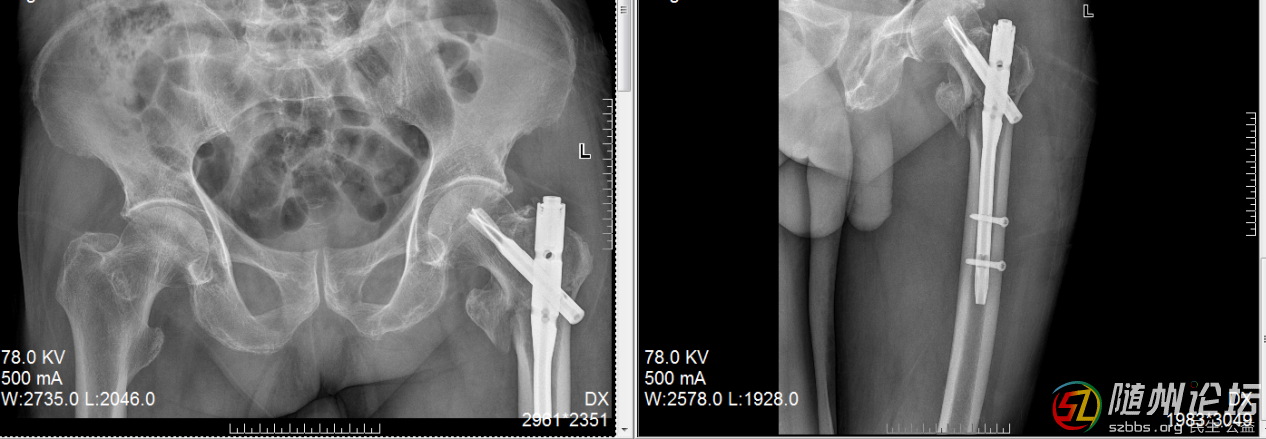

另一位送錦旗的,是一位年過八十的老奶奶,她不慎摔傷了髖部??紤]到患者年紀大、基礎疾病多,創(chuàng)傷骨科啟動多學科會診(MDT),為其制定了完全個性化的手術及康復方案。沒有采用“一刀切”的模式,而是綜合評估其身體狀況、生活需求及家庭支持,選擇了創(chuàng)傷最小、最適合的微創(chuàng)髓內釘固定,并結合中西醫(yī)結合的康復理念,術后早期運用中藥熏蒸等手段活血化瘀、消腫止痛。術后早期功能鍛煉,顯著改善了患者的舒適度,縮短了臥床時間,有效預防了并發(fā)癥,讓老人能重新站立行走。